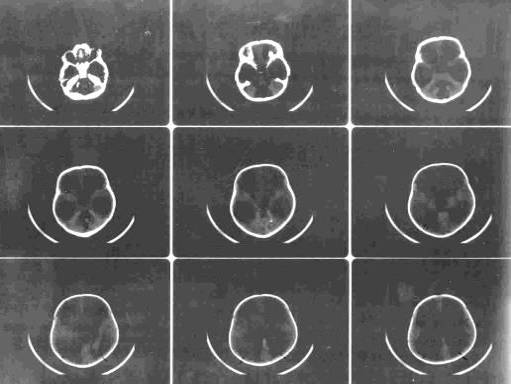

Комп'ютерна томографія (КТ) - у наш

час КТ займає домінуюче положення серед методів діагностики гідроцефалії. Це

технічно складний, але безпечний, надійний і безболісний спосіб діагностики

гідроцефалії. Пучок рентгенівських променів проходить крізь тіло пацієнта, а

зображення внутрішніх органів (у даному випадку мозку) створюються комп’ютером.

Саме дослідження займає від 5 до 10 хвилин. Ш,ь)